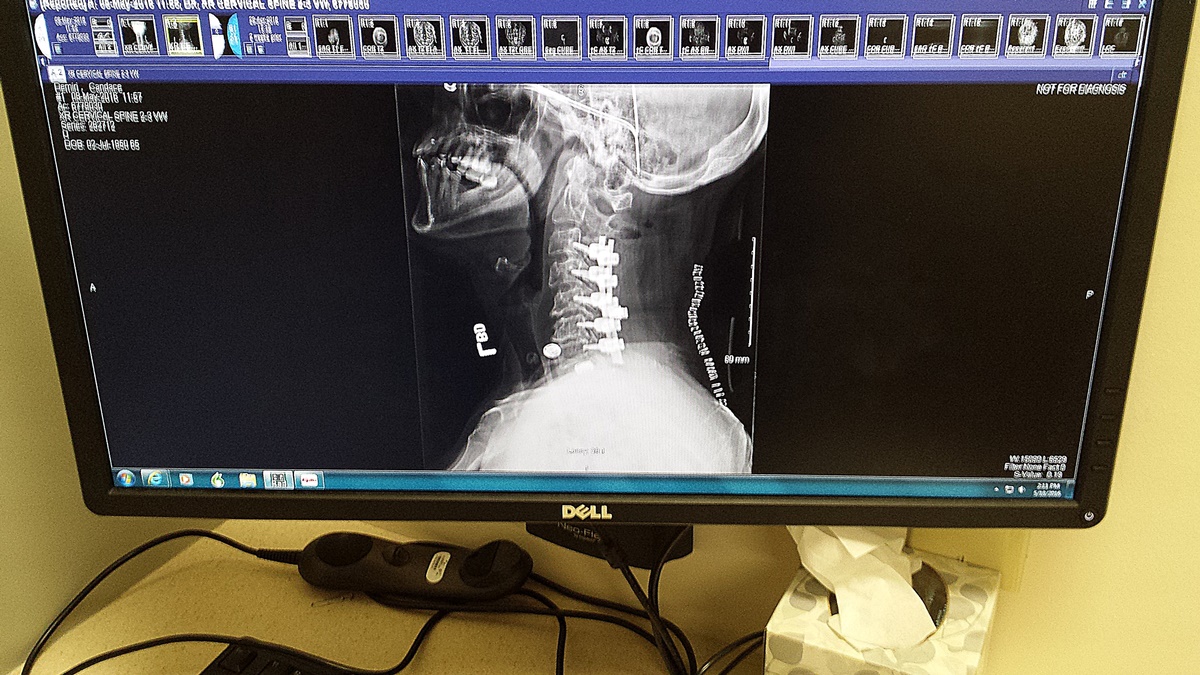

Side x-ray

before staple removal They start at my hairline but they gave me a buzz cut.

Glad daughter is here to help. Many things I can't do yet but I'm getting better. Hurts to sit at the computer for very long, so this will be short. Surgery was the 5th, on lots of pain meds, extreme pain when trying to get up. Pain level 10 when standing. Can you say crying and screaming. Transferred to Rehab on day 4. They discovered my pain level and said they would get that under control first. Finally up and starting therapy after a couple days. After 8 days I was doing well enough to come home. Discharge on the 17th, back to Milwaukee to have staples removed on the 18th....crazy, but they couldn't keep me an extra day. Trip in car was a pain setback but I have recovered. Two therapists come twice a week on alternating days for two weeks.

Wearing a cervical collar until next appointment the second week in June. Hard to eat, hard to chew because of swelling, collar, neck and shoulder pain, but I voluntarily stopped the pain meds. Just using Tylenol. Weak, lost the 10 pounds I wanted to loose but not the way I would recommend. Many issues I had before the surgery have been resolved. Ok, tired now.